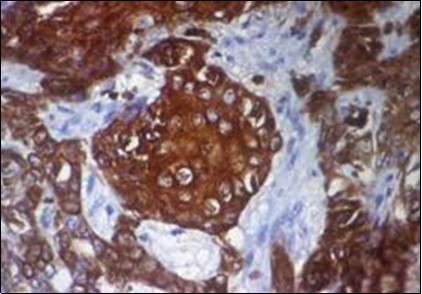

Figure 1.Solid aggregates of tumour cells and duct structures in eccrine porocarcinoma (14).

Solid aggregates of tumour cells and duct structures in eccrine porocarcinoma (14).